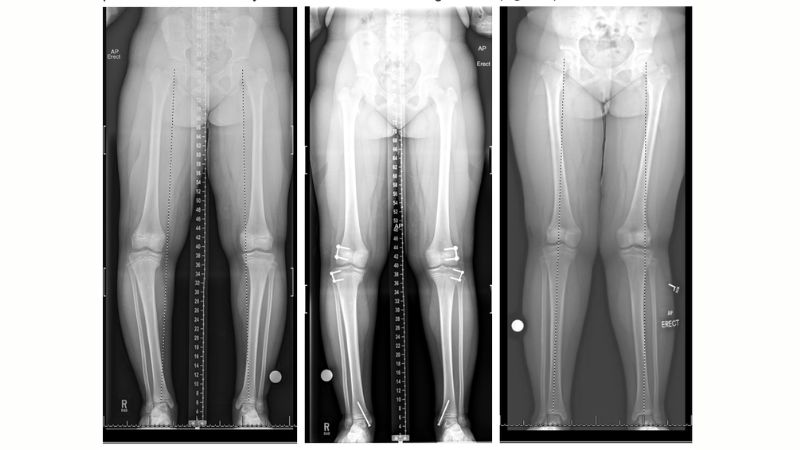

Điều trị bệnh Blount như thế nào?

Có nhiều phương pháp điều trị khác nhau tuỳ theo độ tuổi và tình trạng bệnh. Tuy nhiên, mục tiêu điều trị chung là hướng đến chỉnh lại trục xương, phục hồi dáng chân thẳng và ngăn ngừa biến chứng khớp.

Phẫu thuật

Theo các bác sĩ chuyên khoa, để điều trị bệnh lý này các thao tác sau thường được áp dụng:

- Cắt xương chỉnh trục (Osteotomy): Bác sĩ cắt và chỉnh lại xương chày để đưa về vị trí thẳng. Biến dạng được sửa ngay lập tức, giúp cải thiện dáng đi nhanh chóng.

- Chặn tăng trưởng một bên (Hemiepiphysiodesis): Bác sĩ gắn tấm kim loại nhỏ hoặc ghim vào một bên sụn tăng trưởng (thường là phía ngoài) để ngăn xương phát triển thêm ở bên đó. Trong khi bên kia vẫn phát triển bình thường, xương sẽ dần tự chỉnh về vị trí thẳng.

Sau phẫu thuật, bệnh nhân cần hạn chế đi lại trong 6–8 tuần, tái khám định kỳ để theo dõi sự lành xương và điều chỉnh nếu cần.

Trong một vài trường hợp, bác sĩ sẽ cân nhắc thực hiện phẫu thuật cho bệnh nhân